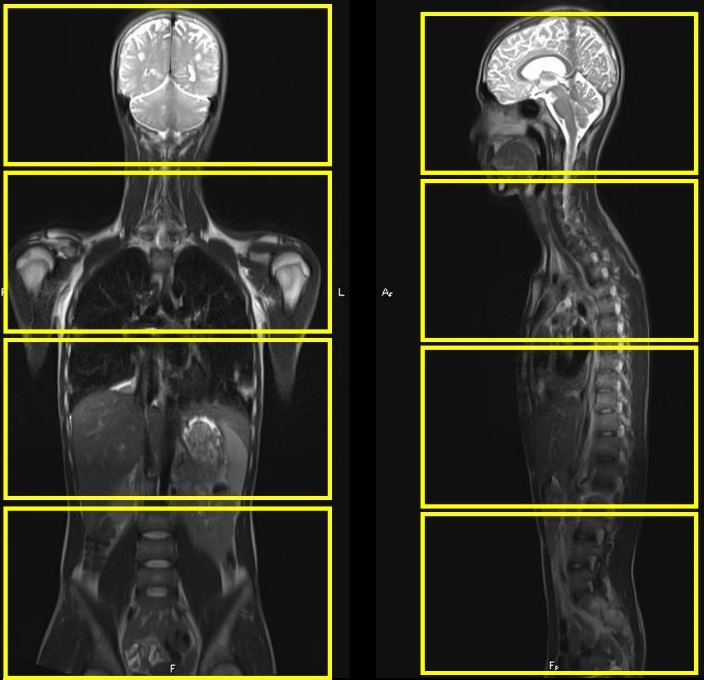

Can thiệp nội mạch điều trị huyết khối tĩnh mạch chủ-chậu phức tạp tại Bệnh viện trường Đại học Y Dược Huế

Vừa qua, Đơn vị Chẩn đoán hình ảnh can thiệp, khoa Chẩn đoán hình ảnh, Bệnh viện trường Đại học Y Dược Huế đã can thiệp thành công một trường hợp...